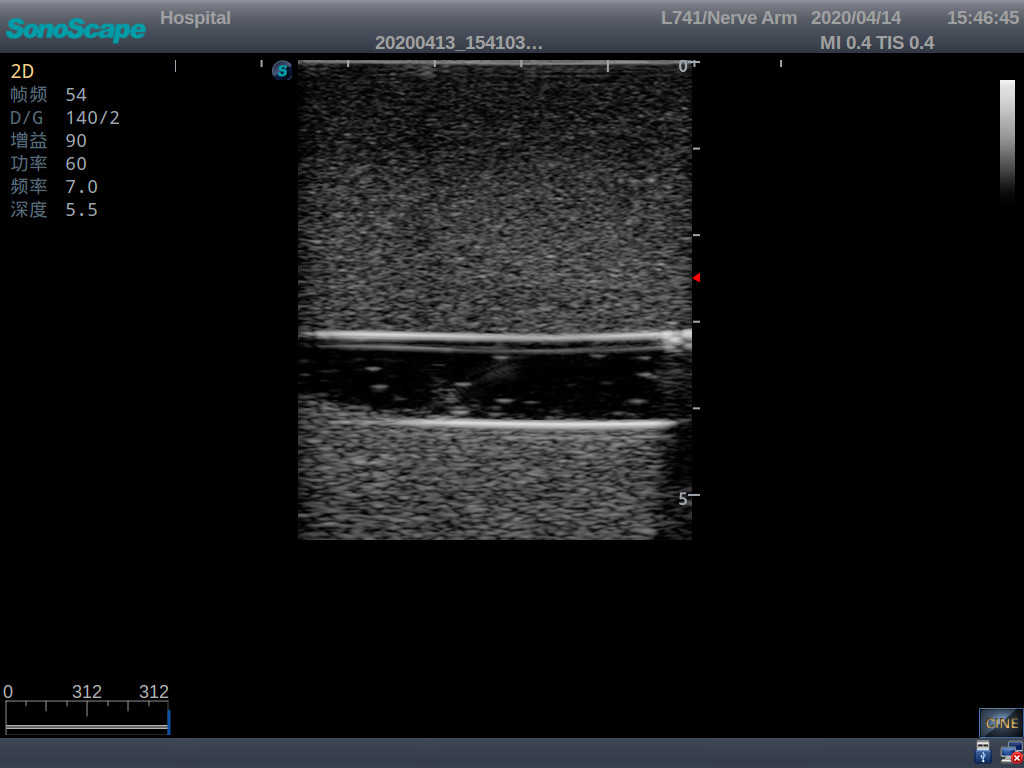

PICC Ultrasound Training Model

Model TYE1510.1

Outline

It is a model covering up from lobulus auriculae plane to the umbilical plane, and it has anatomical structures like clavicle, rib, sternocleidomastoid, jugular vein and basilic vein.

3)   Clear and real images of the tissues and organs (basilic vein and superior vena cava)

5)   Observe the guide wire marches

6)   Detect whether the catheter is properly placed